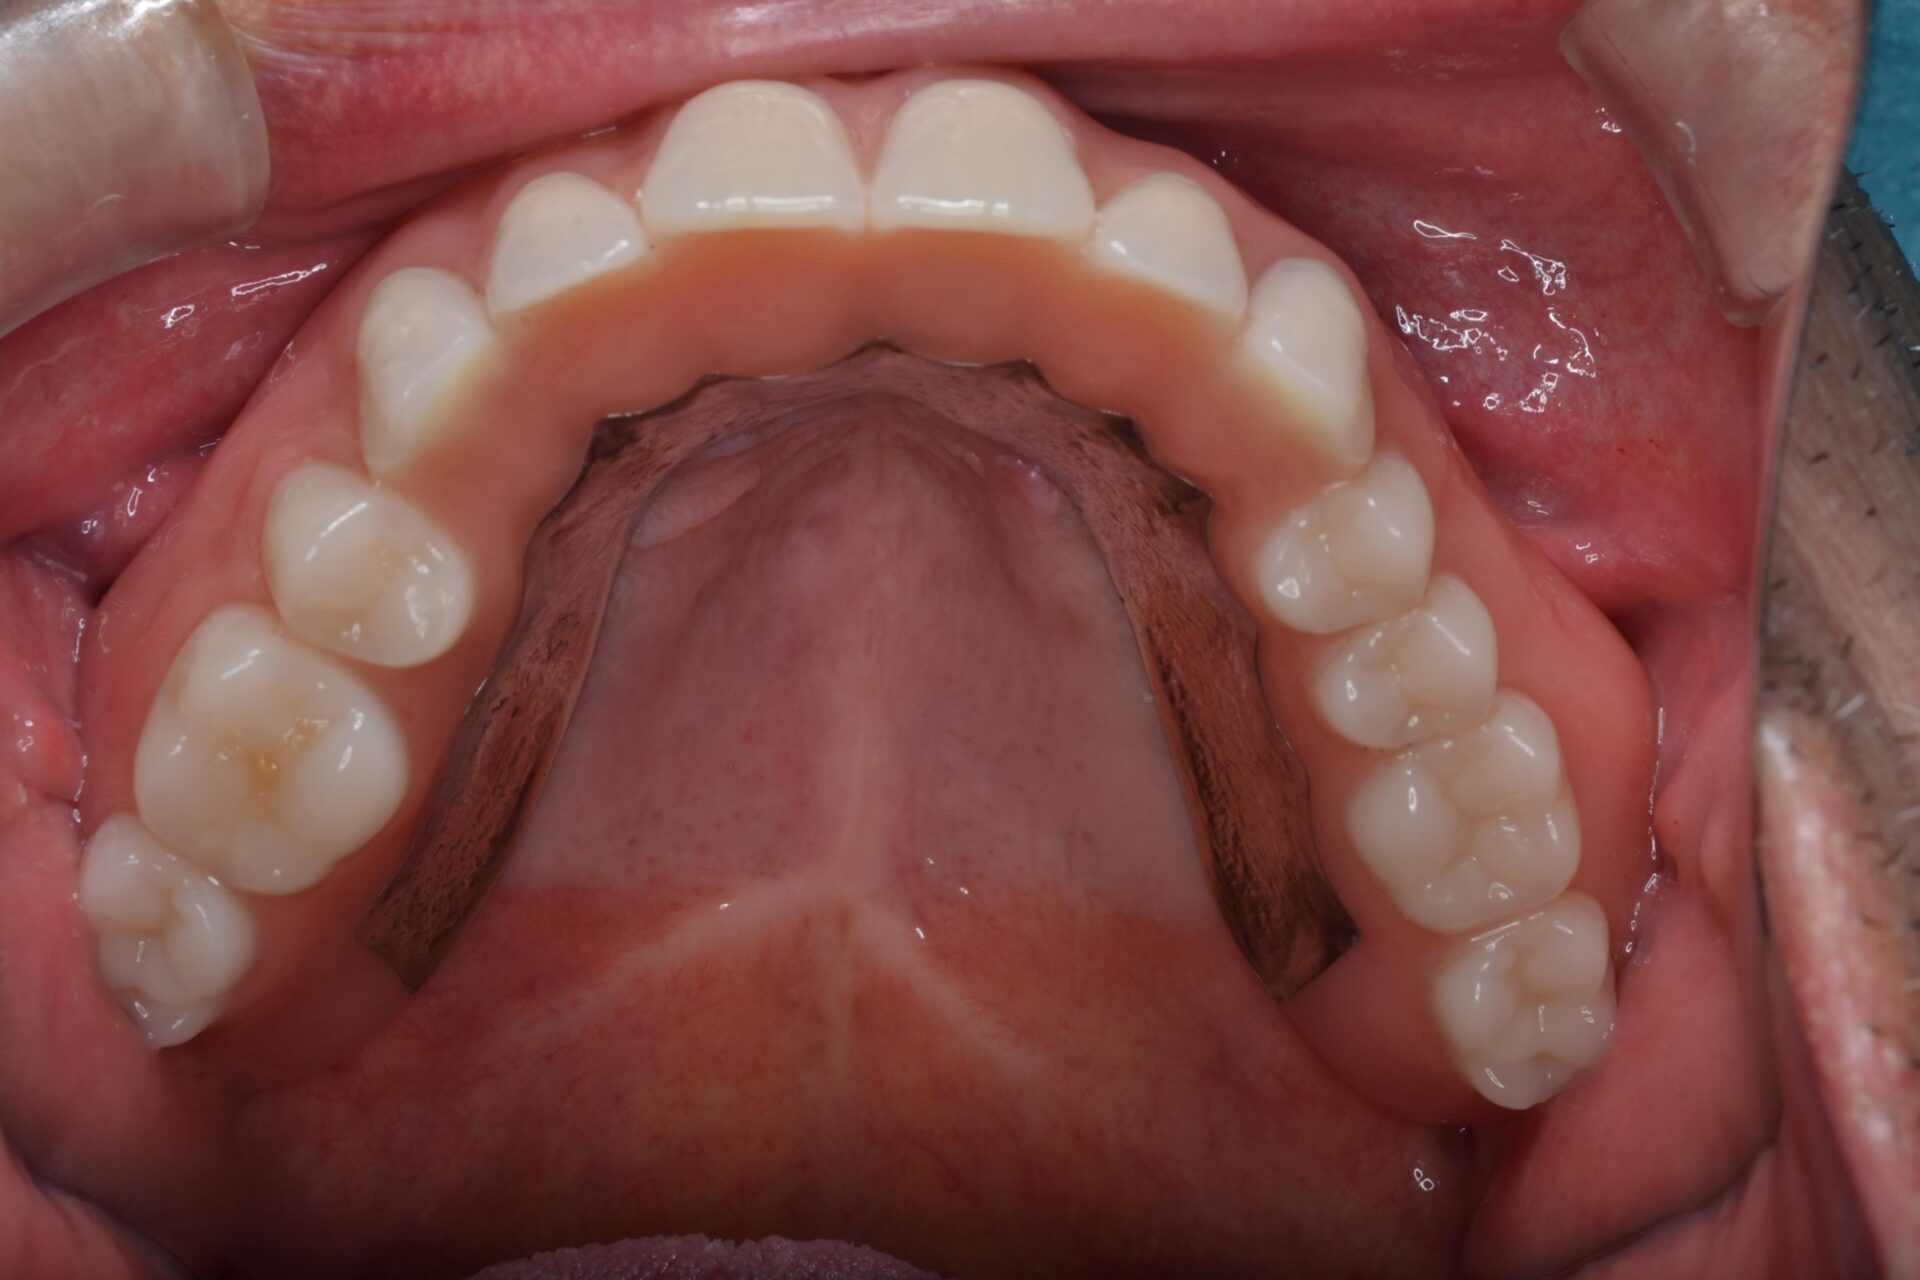

Case

50代 女性

左下の6番目の歯を失われ、その後の治療のご相談に当院にお見えになりました。

インプラント治療は少し恐怖心があるとのことや、隣の歯を削ることにも抵抗があり入れ歯の針金にも抵抗があるとのことで今回はノンクラスプデンチャーという見た目のよい入れ歯を選択頂きました。型取りも含めて2回で治療は終了です。

見た目もよくなんでも噛めるとのことでご満足いただいております。また、少し見える金属の部分に関してはここが非常に重要で、この部分がないと入れ歯は沈み込んでしまい痛みなどがでてしまいます。そのため、沈み込み防止の為にこの部分は必須になります。ここがあるおかげでしっかりと安定しよく噛める入れ歯が完成します。

治療部位 | 左下6 |

費用 | 150000円 |

治療期間 | 1か月 |

注意事項(リスク・副作用など) | 入れ歯を固定する天然歯に負担がかかることがあります。 |

カテゴリ | 入れ歯 |